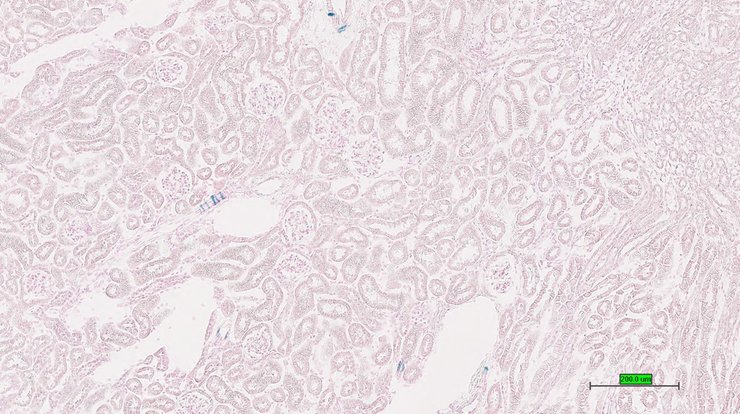

TS28: pancreas Present UC Davis_1883749

Specimen UC Davis_1883750: postnatal adult; Dmp1tm1.1(KOMP)Vlcg/Dmp1+ (more )

TS28: pancreas Present UC Davis_1883704

Specimen UC Davis_1883705: postnatal adult; Dmp1tm1.1(KOMP)Vlcg/Dmp1+ (more )

Structure Level Pattern Image Note

TS28: pancreas Present UC Davis_1883705

Specimen UC Davis_1883706: postnatal adult; Dmp1tm1.1(KOMP)Vlcg/Dmp1+ (more )

TS28: pancreas Present UC Davis_1883706